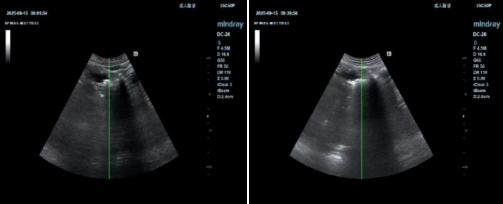

左图:碎石前 右图:碎石后

术后的超声复查显示,胰管内结石已被成功击碎,胰管明显通畅,患者状态恢复平稳,未出现胰腺炎急性发作等并发症,现已顺利返回病房。